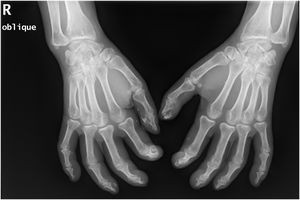

A 50-year-old woman with limited SSc, evolving over 19-years, referred stiffness, pain and ulceration on the first four digital pulps of each hand for one year. She underwent surgical excision of calcium deposits of the 2nd and 3rd fingers bilaterally and started diltiazem 90 mg/day. For two years, there was symptomatic progression. Skin involvement also included sclerodactyly and malar cutaneous telangiectasia. In addition, her SSc was complicated by oesophageal dysmotility, partially controlled with proton pump inhibitors, and severe Raynaud phenomenon (RF), under bosentan. No evidence of pulmonary arterial hypertension or other systemic involvement. Laboratory tests were positive for Antinuclear antibodies (ANA) and anticentromere antibodies (ACA). Physical examination revealed painful, stiff, skin-coloured papules, 4‒10 mm, distributed on the pulp of the 1st, 2nd and 4th right fingers and the 1st left finger, compatible with CC (Fig. 1), as confirmed by hand radiography (Fig. 2). Intralesional STS treatment was proposed due to significant morbidity, progression under diltiazem and the involved site. The procedure was performed using an aseptic technique and under digital nerve block, with a 250 mg/mL solution. Depending on the size of the lesion and pulp distensibility, 0.1‒1 mL of STS solution was injected into the base of the calcifications. Initially, at a 6 to 8-week interval, and after improvement, every 3-months. 25 sessions were performed in 5-years, with continuous symptomatic improvement and better functional status. Hand radiography confirmed a sustained reduction in calcification size (Fig. 3). During the first 2-years, episodes of ulceration and spontaneous drainage of liquified calcium deposits were reported, both self-limited. Additionally, 2 local infections were treated with oral antibiotics. There were no systemic adverse events or analytical abnormalities. However, 2 weeks after the last administration, the patient developed necrosis on the pulp of the 1st right and 2nd left fingers. Treatment with bosentan was suspended 3-months earlier due to long-term control of RF. Oedema from STS infiltration may have triggered a more pronounced RF episode, leading to pulp necrosis. The patient underwent treatment with iloprost 0.4 ng/Kg/min for 3-days and resumed bosentan, with complete healing. Currently, she is asymptomatic, with residual calcifications in hand radiography.